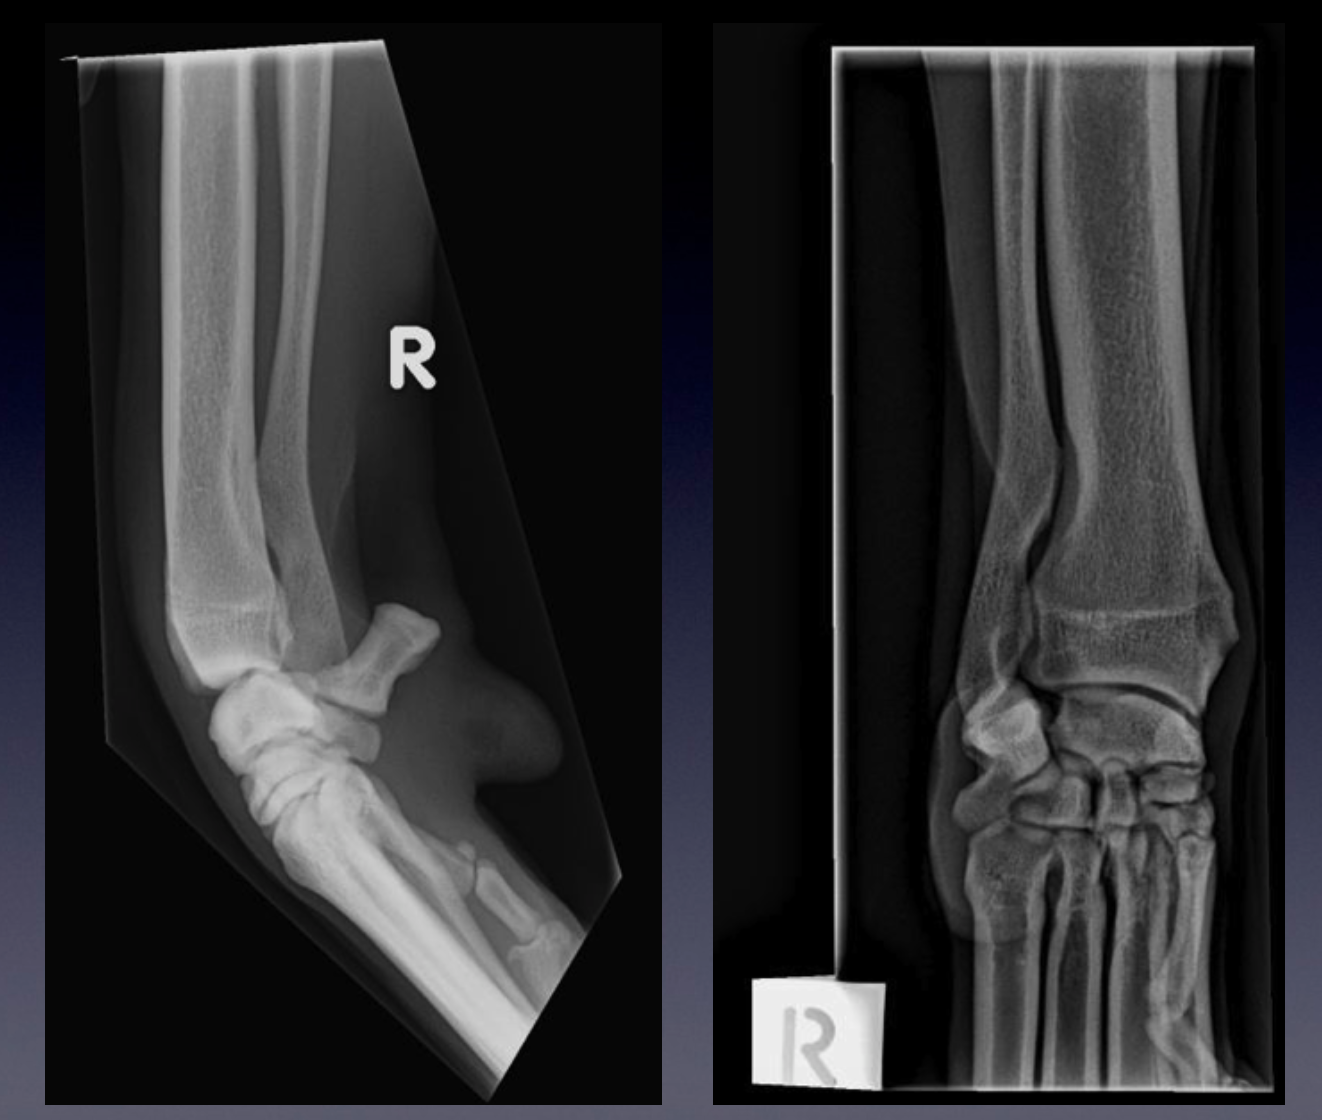

Normal canine elbow

WHICH PROJECTIONS ARE THESE?

Assess positioning:

•

Mediolateral projection

avoid rotation of the humeral condyle

note the humeral trochlea (medial portion) articulates more distally than the capitulum (lateral portion)

Craniocaudal projections

On a well-positioned craniocaudal projection (in this case, of the left elbow), the olecranon of the ulna is

positioned on midline, bisecting the humeral metaphysis and epiphysis.

On a cranio-10°-lateral-caudomedial oblique view (in this case, of the right elbow), the olecranon is

superimposed over the lateral aspect of the distal humerus. This view is sometimes used to free-project the

medial coronoid process.

In addition a ‘neutral’ position mediolateral view may be taken, and is useful for evaluation of the elbow joint congruity.

With this view however, the anconeal process is obscured by the medial epicondyle of the humerus.

Evaluate:

On the mediolateral projection:

The width of the joint space between the humerus and radius, as well as the humerus and ulna

The congruency of the ulna notch and the humeral condyle

The anconeal process for osteophyte formation, and union with the olecranon tuber

The base of the medial coronoid process for sclerosis

On the craniocaudal projections:

The cranial and medial border of the medial coronoid process for osteophytes or fragmentation

The contour of the joint surface of the humerus, for osteochondrosis lesions and sclerosis

The radial head and humeral epicondyles for osteophyte formation

The humeral epicondyles for enthesiophyte formation

Flexed medio-lateral (ML), craniocaudal (CrCd), and Cr10LCdM oblique projections are provided.